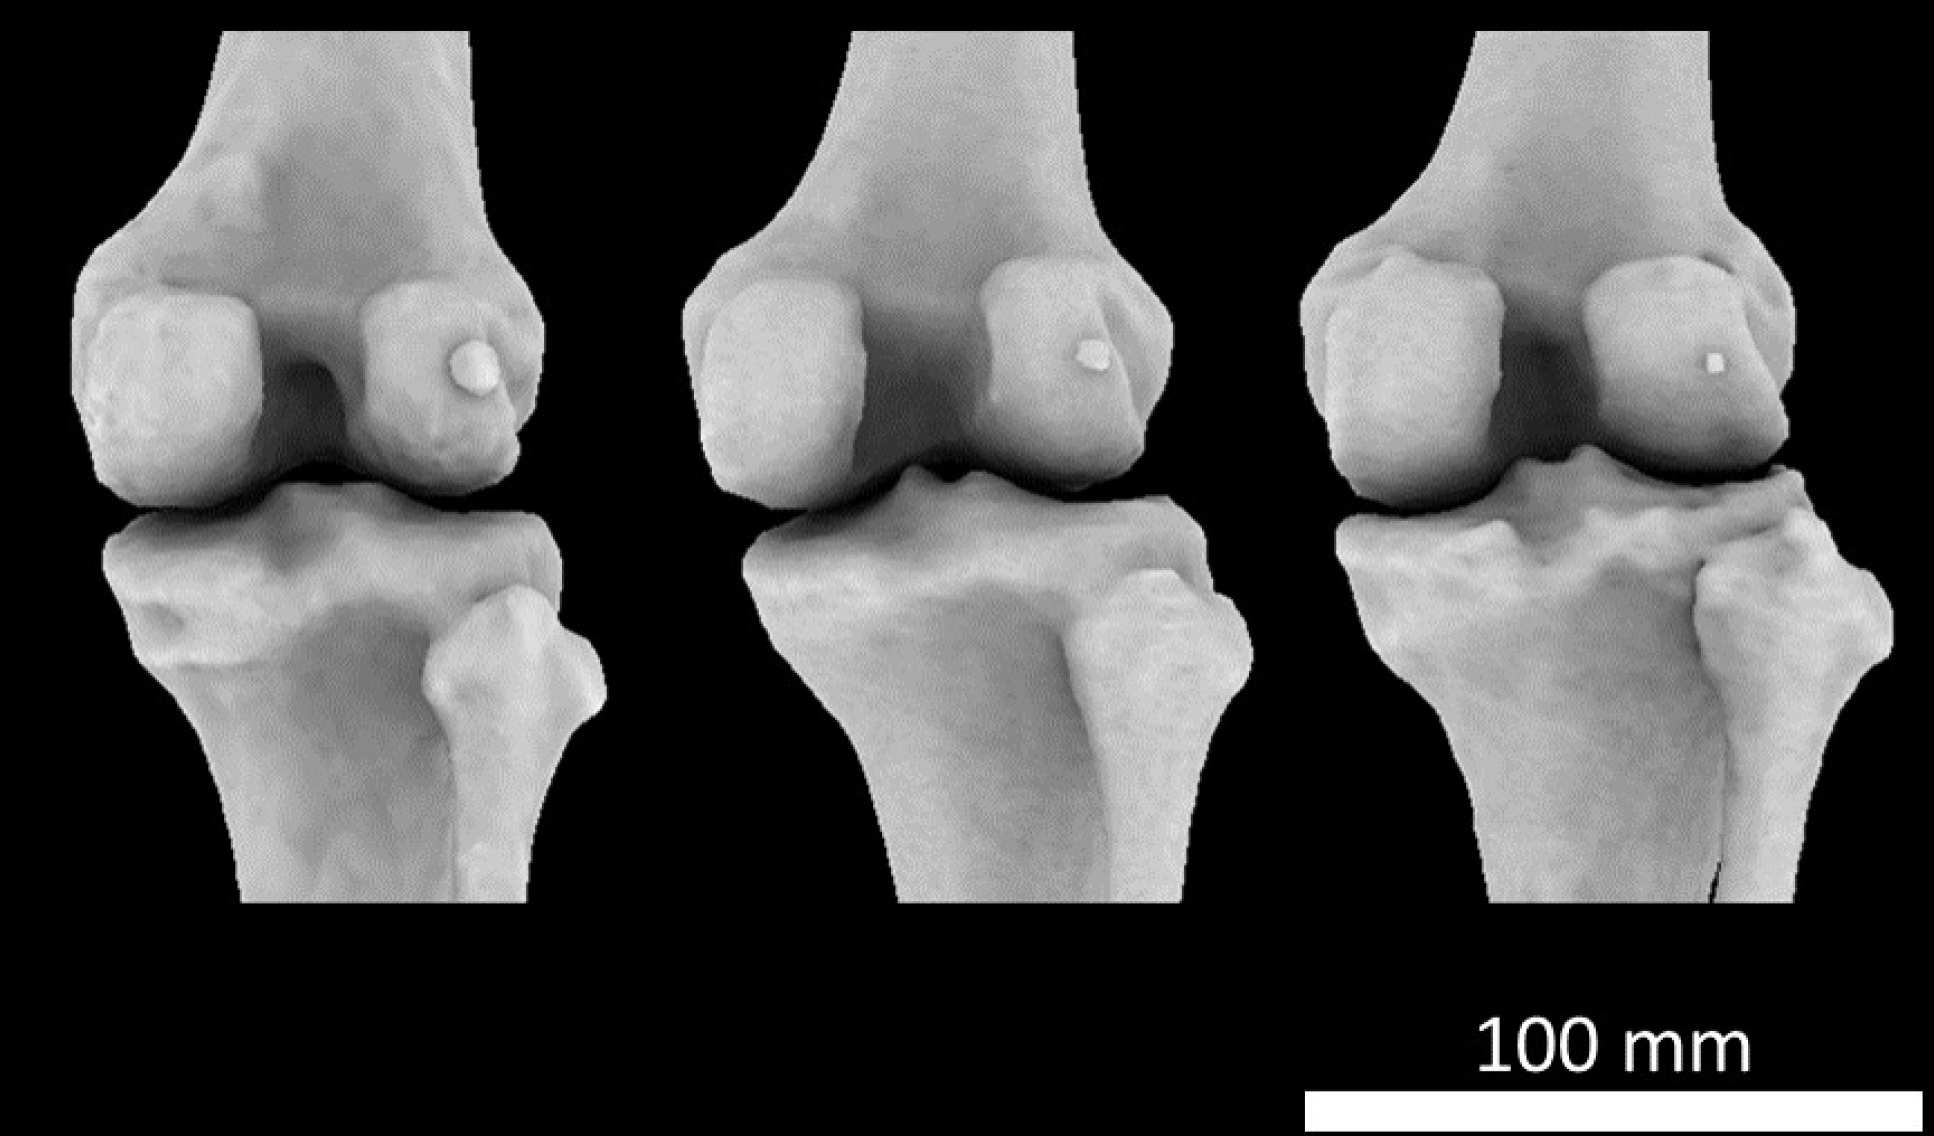

Patella Kneecap Anatomy and Function discount, Knee Bones Anatomy Function Injuries Knee Pain Explained discount, The knee Anatomy injuries treatment and rehabilitation discount, Knee Joint Function Anatomy discount, Where or Where Has My Patella Gone Direct Orthopedic Care discount, Guide to Knee Joint Anatomy Sports health discount, Patellar Fractures Broken Kneecap OrthoInfo AAOS discount, The Knee UT Health San Antonio discount, Normal Anatomy of the Knee Joint Middletown Knee Treatment Old discount, Knee Joint Anatomy Structure Function Injuries Knee Pain Exp discount, Your Knee Just Knees discount, Knee Joint Anatomy and Arthritis SHELBOURNE KNEE CENTER discount, Knee Pain Causes Treatment discount, Detailed Anatomy of the Knee Joint discount, Knee Anatomy and Function Restoration Orthopaedics Restoration discount, Knee Joint Overview Cioffredi Associates discount, Knee Pain What causes it what to do if I have it and how to discount, Patella Wikipedia discount, Kneecap Dislocation discount, Physiotherapy in Calgary for Knee Pain Bipartite Patella discount, Knee pain Wikipedia discount, Knee Trauma Fractures of the Patella Tibial Plateau and Distal discount, The Knee Joint Articulations Movements Injuries TeachMeAnatomy discount, The Kneecap Patella and Knee Joint Saint Luke s Health System discount, Knee Joint Anatomy Structure Function Injuries Knee Pain Exp discount, Knee Anatomy Sweep discount, Matthew Boyle Orthopaedic Surgeon Knee Anatomy Knee discount, Knee replacement Understanding your knee discount, Anatomy of the Knee Worcestershire Knee and Hip Clinic discount, Patellofemoral Pain Syndrome My Family Physio discount, Patellofemoral Pain Syndrome PFPS Symptoms Treatment discount, Kneecap Fractures Patella Fractures Johns Hopkins Medicine discount, Knee anatomy including ligaments cartilage and meniscus discount, Mystery arthritis linked knee bone three times more common than discount, Knee muscle and tendon injuries Chris Bailey Orthopaedics discount.